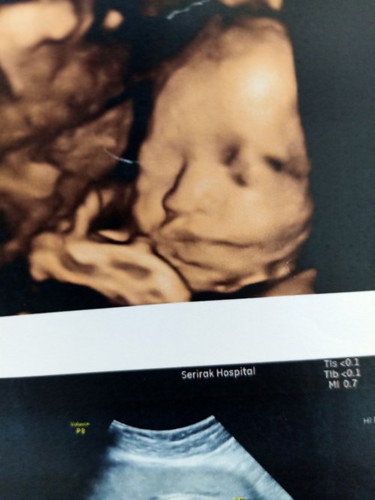

อัลตร้าซาวด์น้อง

ใกล้เข้ามาแล้ว.. 35week

เห็นหน้าน้องชัดเลยค่ะ